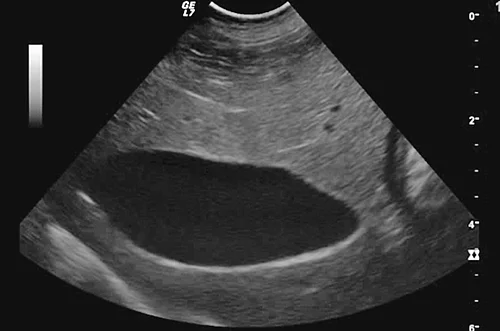

Das Kiwi-Stadium (Abb. 4) ist dagegen vor allem durch die hochgradig verdickte und auffällig lamellierte Wand und zentral gelegenem echogenem Sludge charakterisiert [8]. Das Stern- und Kiwi-Stadium sind verschiedene, voneinander unabhängige Manifestationen einer MZ.